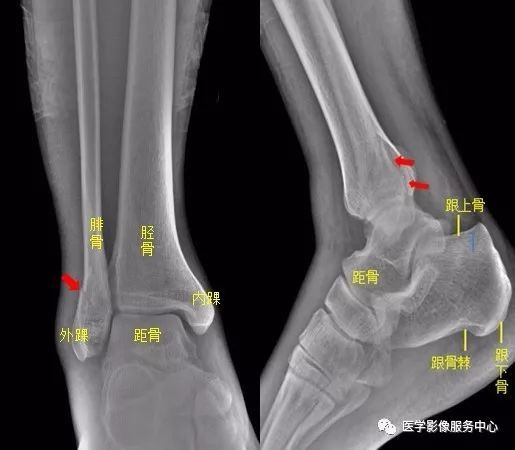

独立值班了 这些骨折你都看出来了吗 附注解 会议中心

收藏 独立值班 这些骨折你都看出来了吗 附注解 移位

独立值班了这些骨折你都看出来了吗 附注解 腾讯新闻